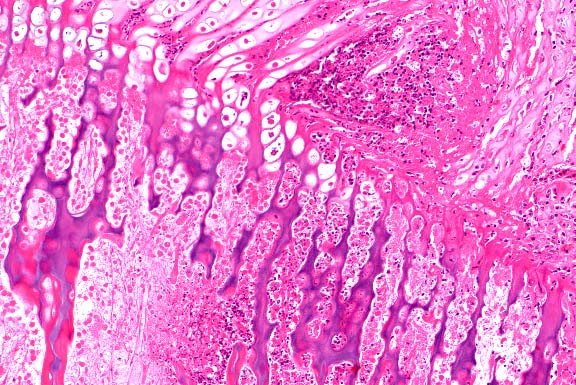

- Microscopic examination revealed a tumor-like mesenchymal

proliferation consisting of chondrocytes forming a rim of hyaline

cartilage surrounding spongy bone. The cortex of each growth

was irregular, and the spongy bone had trabeculae supporting

fatty marrow. Remnants of cartilage persisted in the osseous

mass. The histological picture suggests a peripheral chondromatous

proliferation followed by imperfect central endochondral ossification.

- Case 20-2. Bone. Irregular endochondral bone formation

occuring deep within cancellous bone. Dark cells in the lower

right are osteoclasts.

- Histologically, osteochondromas of dogs and horses recapitulate

the zones of development found in the normal epiphyseal growth

plate. Microscopic examination reveals a variably thick cartilage

cap with scattered areas of mineralization covered by a thin

layer of fibrous periosteum. The cap of hyaline cartilage is

bordered at the base by regularly arranged cancellous bone which

is produced by orderly endochondral ossification in actively

growing lesions. Trabeculae of cancellous bone are separated

by marrow elements. In old lesions in adult animals, extensive

endochondral ossification may result in little or no cartilage

remaining at the apical surface. Feline osteochondromatosis differs

microscopically from the inherited condition in young dogs and

horses in that the cartilage is irregular, chondrocytes are haphazardly

arranged, endochondral ossification is less orderly, and the

hyperplastic periosteum may directly form bone.